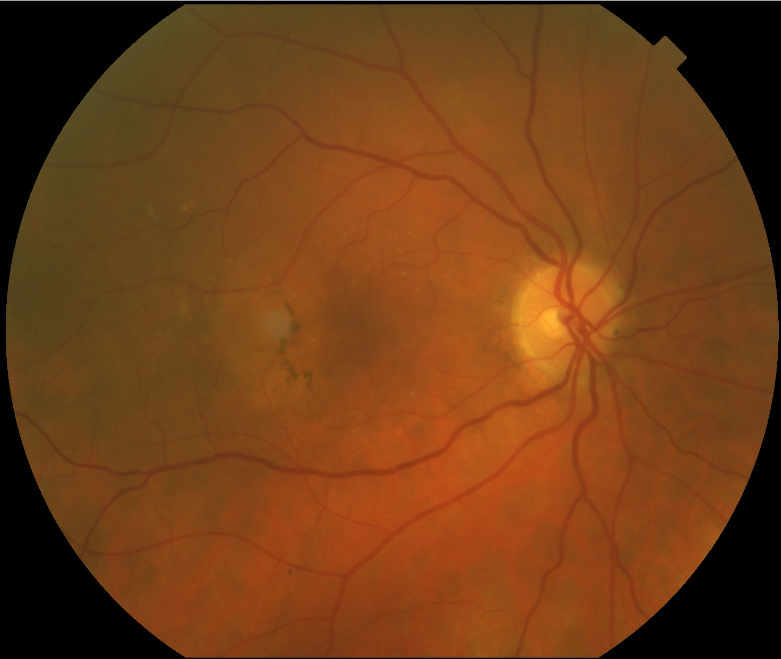

FUNDUS DESCRIPTION: |

OD OS |

OD Red-Free: Pre-Injection: Arterial: A-V: Venous: Recirculation: Late:

OS Red-Free: Venous: Recirc: Late:

Impression